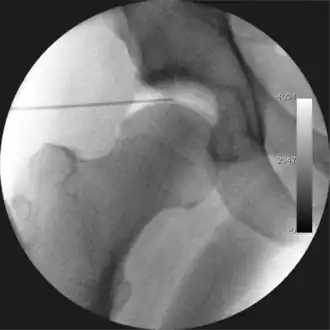

Figure 3. Fluoroscopic picture showing a mild amount of distraction of the hip before insertion of any instruments

Figure 4. A needle is passed into the joint, breaking the 'suction seal', and allowing further distraction of the hip joint with minimal extra traction

The procedure is performed with the patient asleep (general anaesthetic) or under spinal anaesthesia. There are two widely used methods, one with the patient on their back (supine) and the other on their side (lateral decubitus). Which is used is down to the surgeon's preference. To gain access to the central compartment of the hip joint (between the ball and socket), traction is applied to the affected leg after placing the foot into a special boot. (See fig. 2) There is specifically designed equipment for this, although some surgeons use a 'traction table', initially designed to help in the operative fixation of broken thigh and lower leg bones. The amount of traction (or pull) needed is assessed with the help of fluoroscopy (low-dose portable x-ray). (See fig. 3) It is usually not possible to distract the ball from the socket with traction alone by more than a few millimetres. Once the surgeon is happy that they will be able to gain access to the hip joint (i.e. the ball will distract from the socket by a small amount), the patient is then painted with antiseptic and the surgical drapes applied.

The next step is to insert a fine needle under x-ray guidance into the hip joint. This breaks the 'suction seal' of the joint and allows further distraction if necessary (see fig 4). The surgeon wishes to see the ball move out the socket by approximately 1 cm, so that access to the hip joint can be achieved with minimal risk of damage to the joint surfaces. Most surgeons will inject fluid into the joint at this stage, again to ensure that there is enough space between the ball and socket for safe instrument access. This needle is then removed. The next step is placement of the 'portals', or the small holes made to pass instruments into the joint. This is achieved by again passing a fresh hollow needle into the joint under x-ray control, usually in a slightly different position. The reason for this is so the surgeon can ensure that the needle, and subsequent cannulae do not penetrate and damage the acetabular labrum or cartilage joint surfaces (see fig. 5). Again, surgeons will have their own preferences as to their preferred placement. Through this hollow needle, a long thin flexible guide wire is passed into the joint, and the needle is removed over it, leaving the guide wire in situ. A small cut in the skin is made around the wire, to allow for larger cannulae to be placed over the wire through the portal. The wire therefore guides the larger cannulae into the joint. The most common external diameters of cannulae used are between 4.5 and 5.5 mm. Once the surgeon is satisfied that the cannula is in the correct position, by a combination of feel and x-ray guidance, the guide wire can be withdrawn. Once the first portal is correctly placed, any further portals may be created once the camera is in position, to ensure that they are placed with minimal risk to the joint surfaces. This process can be repeated to gain as many points of entry to the hip joint as the surgeon requires, normally between two and four. Certain of these entry points will be used for the viewing arthroscope and others for operating instruments.